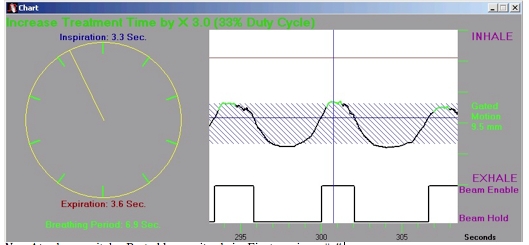

Atemabhängige Bestrahlung-Atemgating

Die Organe im Brust- und Bauchbereich sind häufig atemverschieblich. Zur Bestrahlung müssen deshalb Sicherheitssäume eingeplant werden. […]